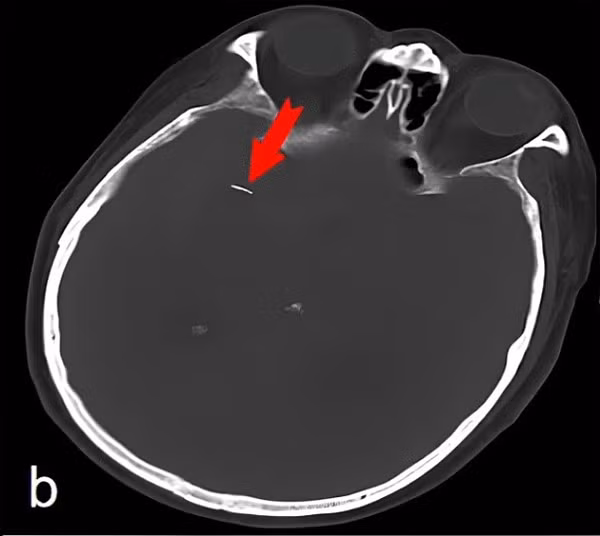

| Dị vật trong não bệnh nhân Trung Quốc. Ảnh: Daily Mail |